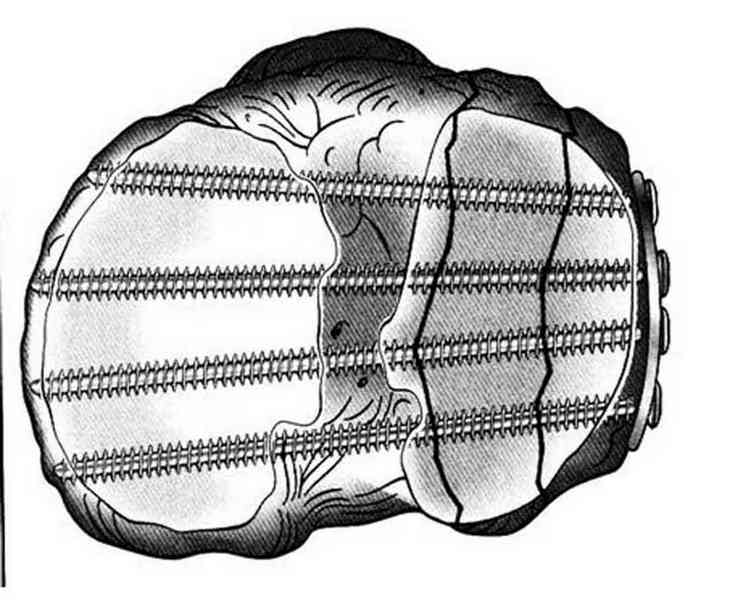

Основная задача в лечении околосуставных переломов является создание солидного базиса в субхондральной зоне. Пластина подпорка (Butress) или субхондральные перкутанные шурупы в виде плота (Raft) для ранних движении.

У больного двухстороннее повреждение, ограничен в нагрузке не менее 8-10 недель. После односторонней фиксации будет активным, хотя бы в пределах койки. Без спешки дождаться улучшения кожных покровов, и аппаратом Илизарова в комбинации с шурупами или спицами, из мини-доступов.

Все названные пластины не пригодны для фиксации мельких фрагментов. Сейчась многие компании имеют периартикулярные пластины достаточной длины с возможностью установки в мульти аксиальном направлении более тонкими шурупами вместо 3.5мм. Шурупы 2.7 мм не раскалывая позволяет удержать фрагменты в дистальном сегменте.

Пластина от DePuy отвечает всем требованиям, но могут быть и другие варианты. Репозицию закончивается костной пластикой или заполнением синтетическими заменителями иначе поведет в варус.

Отсутствие материала не причина не делать хорошую репозицию, или лучше перевести больного туда, где больше возможностей. Александр прав, вместо пластины предпочтительным будет фиксировать аппаратом Илизарова.